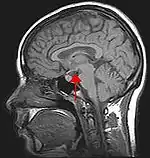

روانشناسی بیولوژیکی به مطالعه علمی بسترهای بیولوژیکی از رفتار و حالات ذهنی میپردازد. روانشناسی زیست شناختی بخشی از روانشناسی است که سعی در درک و روشن کردن عملکردهای روانشناختی با فرآیندهای بیولوژیکی دارد. به عنوان مثال ، نحوه عملکرد مغز و سیستم عصبی بر افکار ، رفتارها و احساسات ما تأثیر می گذارد.